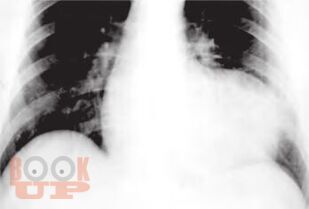

Общая методика обследования больного известна выпускникам медицинского вуза. Однако в каждой специальности имеются вопросы, для ответа на которые применяются дополнительные методы исследования. Пациенты, готовящиеся к операции на сердце, требуют особого подхода ввиду сложности патологии и высокого риска возникновения угрожающих жизни осложнений. Чтобы не упустить важную информацию, необходимо знать специфику кардиохирургической патологии и тот оптимальный набор исследований, который позволит предусмотреть возможные риски. Методические рекомендации по ведению пациентов с показаниями к операции отражены в настоящем издании.